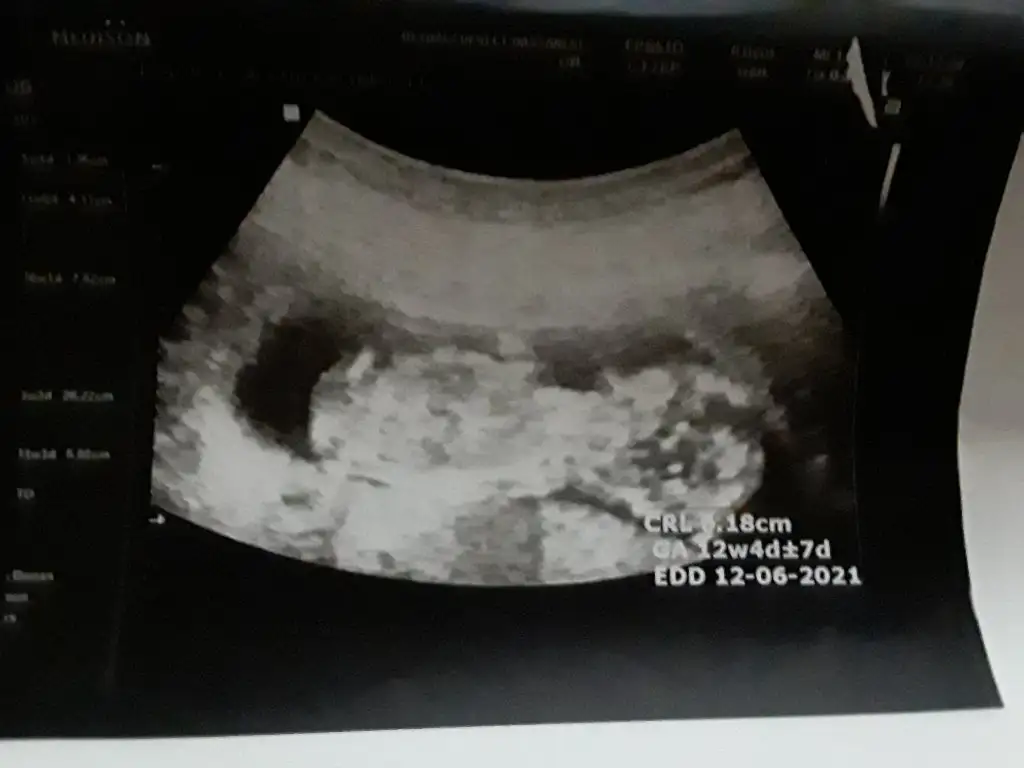

Erkeğe benziyor goruntusuKizlar 12 haftalik bebegimin cinsiyet tahmini yapar misiniz cok merak ediyorum :) Eki Görüntüle 2685687